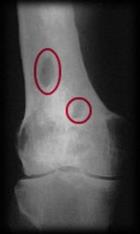

Реактивне запалення навколо секвестру виражається в розвитку грануляційного вала, а з боку періосту – в запальному потовщенні окістя – характерна ознака остеомієлітичного процесу. На межі між живою і мертвою тканиною як з боку діафізу, так і з боку губчатої речовини гаверсових каналів і кісткового мозку утворюється грануляційний вал – демаркаційна лінія поміж нормальною та некротизованою кісткою; при рентгенологічному дослідженні демаркаційна лінія має вигляд світлої зігзаго-подібної полоси.